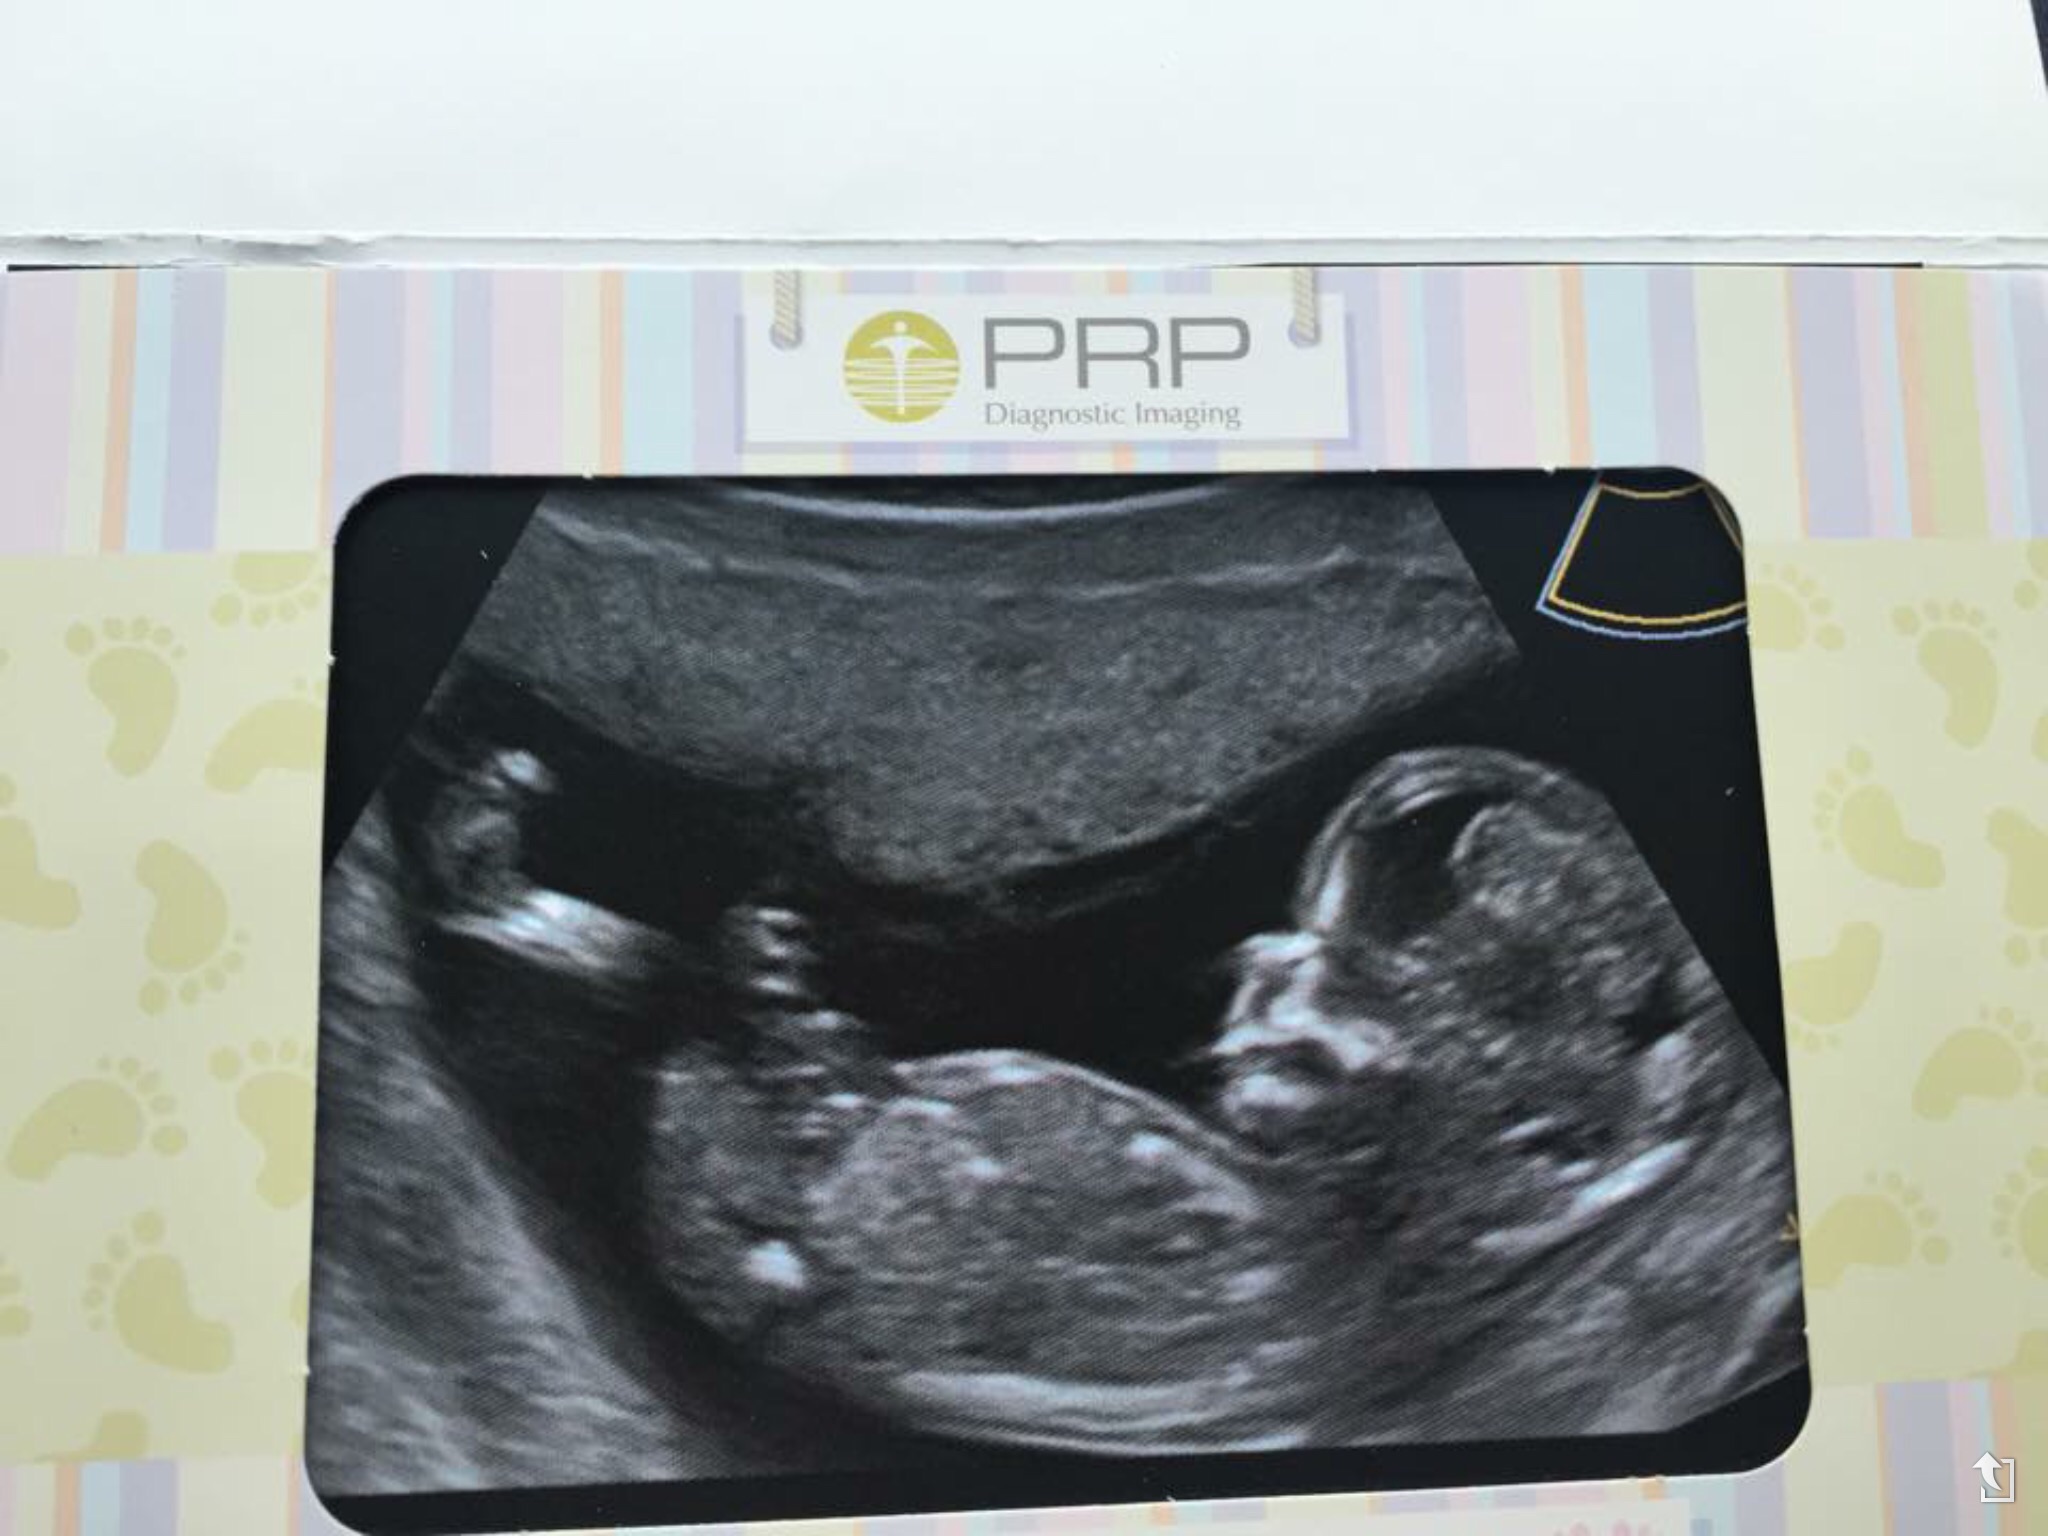

Posting for a friend Attachment 26709

Any guesses?

I'm not seeing a nub sorry

no nub visible, more pics?

BOY LEAN